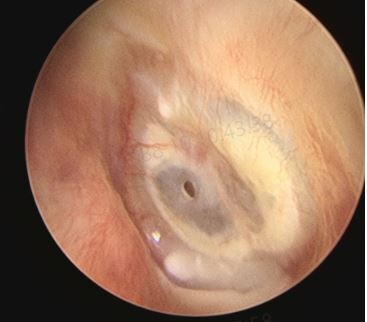

最近遇到一些關(guān)于鼓膜穿孔的爭(zhēng)論,醫(yī)患的角度不同,理解不同,醫(yī)生可以很理性,而患者牽涉自身,往往很感性。非常理解,但是知識(shí)相通才可以構(gòu)建交流的橋梁。所以,關(guān)于鼓膜穿孔這件事兒,想給大家普及一點(diǎn)知識(shí),以便大家可以理性健康的對(duì)待我們的耳朵??耳從解剖角度分外耳、中耳及內(nèi)耳,鼓膜位于外耳道底部,與外耳道有一個(gè)大約45度的夾角,鼓膜的主要作用是聲波傳導(dǎo)作用,由于鼓膜的解剖位置及外耳道與中耳腔微生物環(huán)境的不同,鼓膜也有分界外中耳,起到楚河漢界的作用。最常見的鼓膜穿孔的因素有兩類,一類是耳外傷,另一類是急性炎癥。耳外傷常見的有不良挖耳習(xí)慣損傷,比如掏耳朵不慎棉簽捅入鼓膜導(dǎo)致?lián)p傷,此外,還有打架耳光損傷以及一些重大交通事故損傷。另一類導(dǎo)致鼓膜穿孔的因素多為感染,急性上呼吸道感染后引發(fā)急性中耳炎,耳痛劇烈,流膿,流膿后耳痛減輕。尤其是在兒童期,夜間發(fā)熱、耳痛,急診檢查鼓膜充血紅腫,用藥一兩天發(fā)現(xiàn)耳道內(nèi)多量血性分泌物,大多為急性炎癥刺激導(dǎo)致鼓膜穿孔,檢查可以見到鼓膜表面有光點(diǎn)波動(dòng)—俗稱燈塔征,是中耳膿性分泌外涌的表現(xiàn)。亦有部分反復(fù)發(fā)作的慢性外耳道炎患者,多有不良掏耳習(xí)慣,反復(fù)挖耳或者清理沖洗,炎癥初始分布外耳道,后進(jìn)一步波及鼓膜,導(dǎo)致鼓膜表面有炎癥滲出及肉芽生長(zhǎng),鼓膜菲薄,外力作用或炎癥進(jìn)一步刺激,可導(dǎo)致鼓膜穿孔。鼓膜的生理作用為傳音、分界外中耳的作用,當(dāng)發(fā)生鼓膜穿孔后,鼓膜的傳音作用受到影響,故而多數(shù)穿孔患者都有一定程度的聽力損失。國(guó)內(nèi)外學(xué)者的研究顯示:穿孔越大,聽力損失越重。大部分鼓膜穿孔都有25-40分貝左右的聽力損失,當(dāng)然,鼓膜穿孔導(dǎo)致的聽力下降,也與中耳容積及中耳粘膜的狀態(tài)有關(guān)系。此外,由于外中耳的楚河漢界被破壞,外耳道與中耳腔相通,外源性的感染因素可以直接進(jìn)入中耳,導(dǎo)致中耳炎的發(fā)生。同時(shí),中耳腔被覆粘膜組織,而外耳道是上皮為主,兩者在酸堿度及濕度上均有不同,外中耳交通,易導(dǎo)致外耳道炎癥的發(fā)生。外傷因素導(dǎo)致的鼓膜穿孔,多為裂隙狀、不規(guī)則形穿孔,治療上要求患者保持外耳干燥、禁用滴耳液,適當(dāng)抗炎預(yù)防感染,大多數(shù)外傷性鼓膜穿孔多在兩周到一個(gè)月左右愈合,如果超過三個(gè)月沒有愈合,考慮外傷性鼓膜穿孔無法自愈,就需要進(jìn)一步手術(shù)干預(yù)。穿孔的愈合過程為鼓膜表面上皮向?qū)?cè)爬行的過程,最終會(huì)使不規(guī)則形狀的穿孔愈合。上皮爬行過程可使鼓膜穿孔相鄰邊緣愈合,上皮進(jìn)一步向內(nèi)側(cè)爬行,由不規(guī)則的穿孔,變?yōu)閳A形、橢圓形、腎形或者馬蹄形。故而,慢性反復(fù)發(fā)作的中耳炎,多難自愈,其穿孔也多為近圓形、橢圓形或腎形的。穿孔的病理狀態(tài)存在,使中耳腔不定期處于感染狀態(tài),或有反復(fù)流膿的,也有炎癥過度反應(yīng),使鼓室內(nèi)粘膜玻璃樣變性,進(jìn)而進(jìn)一步導(dǎo)致聽力下降,這就是中耳炎最常見的并發(fā)癥--鼓室硬化。故而,對(duì)于鼓膜穿孔的患者,建議患者選擇合適的時(shí)機(jī),行手術(shù)修補(bǔ)。

來自廣東佛山禪城的劉女士由于左側(cè)耳流膿伴聽力下降多年了,一直想做耳內(nèi)鏡中耳炎微創(chuàng)手術(shù),但是平時(shí)比較忙一直沒有時(shí)間。另一個(gè)還是非常擔(dān)心手術(shù)的效果,所以許多醫(yī)生建議她手術(shù),她一直想做但是怕醫(yī)生的技術(shù)不好,做了聽力不但沒提高,還下降了,就會(huì)給自己的生活造成非常大的影響。在再三比較和考慮后,她來找耳鼻喉鄭立崗醫(yī)生,對(duì)鄭醫(yī)生的技術(shù)她是非常信任的,一個(gè)是她多次來就診過,也看過之前中耳炎手術(shù)的患者對(duì)于鄭醫(yī)生的一些評(píng)價(jià),所以她最終還是決定來找耳鼻喉鄭立崗醫(yī)生主刀做自己的中耳炎手術(shù)。入院后安排了全麻耳內(nèi)鏡左側(cè)中耳炎微創(chuàng)手術(shù),插管全麻后就開始了手術(shù),耳內(nèi)鏡下不用做任何的體表切口,直接翻起外耳道鼓膜皮瓣,翻起皮瓣后可以看到鼓室中無肉芽及膽脂瘤組織,聽骨鏈?zhǔn)峭暾?,活?dòng)可,取合適大小的耳屏軟骨修剪后修補(bǔ)鼓膜,鼓膜修補(bǔ)好后檢查了兩遍確認(rèn)沒問題后就結(jié)束了手術(shù)整個(gè)的手術(shù)用時(shí)約50分鐘,非常的順利。術(shù)后查房患者無明顯的不適,無手術(shù)相關(guān)的并發(fā)癥。對(duì)于中耳炎微創(chuàng)手術(shù),一般來說手術(shù)的難度不算特別大,但是找一個(gè)技術(shù)成熟的醫(yī)術(shù)是手術(shù)效果的最好的保障。